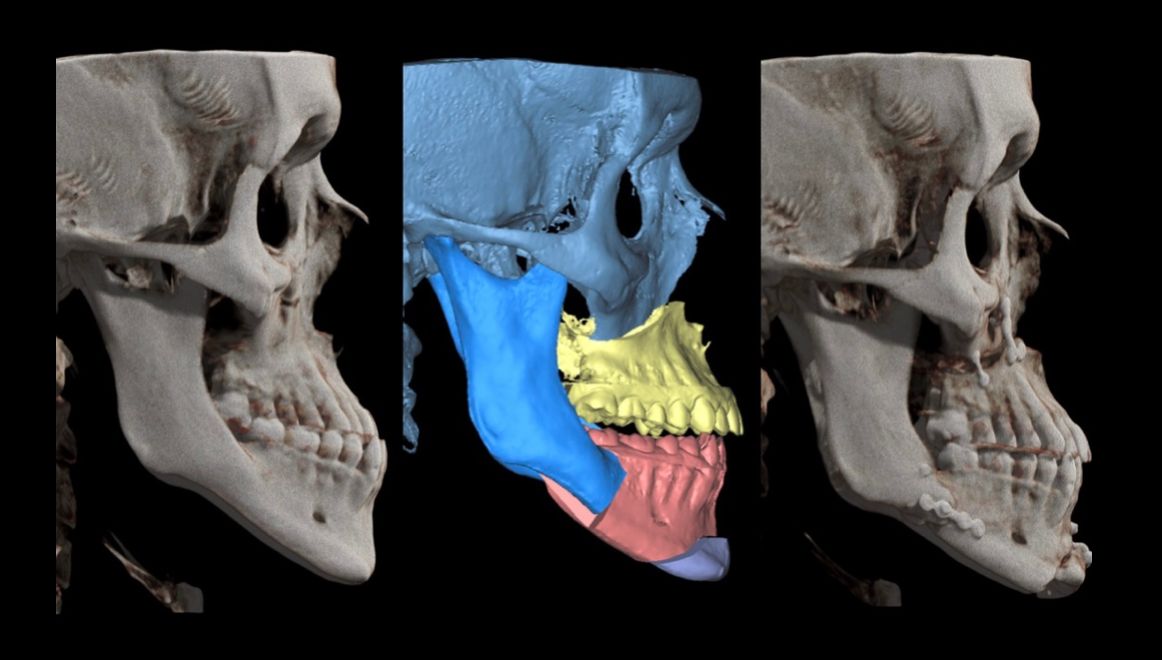

¡Hola! Soy el Dr. Emmanuel Guerrero Soto, Cirujano Oral y Maxilofacial con Mención Honorífica por el Hospital Central Militar, Master en Cirugía Ortognática por la Universidad Francisco de Vitoria de Madrid, España, Fellow también en Cirugia Ortognática por parte de Ortognatica Roma, Italia; y Fellow en Implantología Quirúrgica con estudios en Vitoria, España. Conmigo tendrás un trato humano, paciente y efectivo. Para conocer más sobre nuestro trabajo y ubicaciones, visita nuestra pagina de Instagram.

- Cirugía ortognática y estética

Experto en Ortognática e Implantes dentalesMaster/Fellow Internacional en Cirugía Ortognática+10 años de experiencia extrayendo 3ros molares

Soy paciente postoperada de cirugía ortognática , antes pensaba que tal vez la cirugía ortognática ya no era opción para mi por mi edad y porque estaba "camuflajeada" con ortodoncia aunque no me sentía bien. El Dr. Emmanuel aclaro todas mis dudas sobre la cirugía, trabajó coordinadamente con mi ortodoncista para que estuviera en condiciones adecuadas para la cirugía, estuvo pendiente en todo el proceso, siempre me sentí tranquila y confiada por su profesionalismo y paciencia para resolver mis dudas respecto al plan de tratamiento quirúrgico.

Estoy cursando mi segunda semana post operada , ya puedo ver los cambios y me siento muy bien. Operarme fue la mejor decisión que pude tomar y sin duda el Dr. Emmanuel es un especialista altamente calificado para tratar defomidades dentofaciales.• Momentum Centro Sur, Torre 2, Consultorio 209 • Cirugía ortognática •